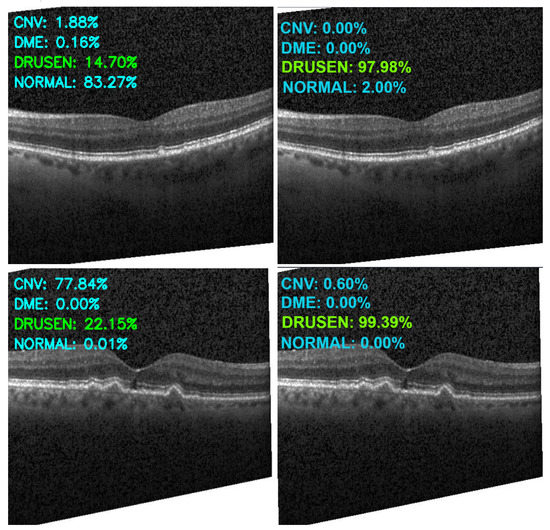

Figure 13, Figure 14, Figure 15 and Figure 16 show several examples of the proposed model performance (accuracy and classification confidence score) on OCT images using the original and augmented dataset-trained model, respectively.

Figure 14.

Exemplary result of proposed model trained without (left column) and with (right column) augmentation (correct label highlighted in green).